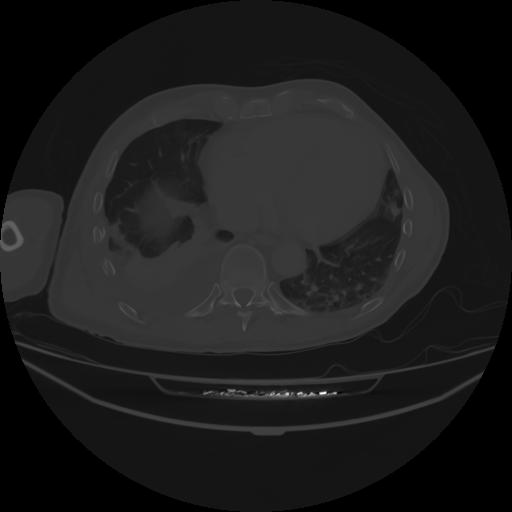

4 CUERPO,CE,Axial,3.0,CUERPO,,